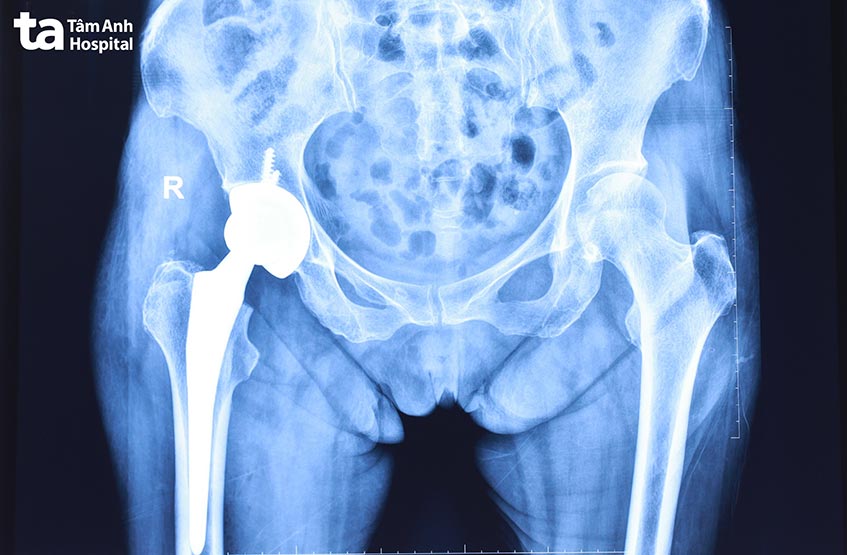

Tái khám sau 1 tháng, bà Phương cho biết khớp háng đã có thể vận động bình thường. Tuy nhiên, lúc này khớp gối sưng to và đau nhiều, ảnh hưởng đến việc đi lại. Phim chụp X quang cho thấy người bệnh bị thoái hóa nặng ở khớp gối bên phải. Khớp đã bị biến dạng, vẹo trục 10 độ, có rất nhiều gai xương và hẹp khe khớp hoàn toàn. Người bệnh được chỉ định thay khớp gối để khôi phục tối đa chức năng và khả năng vận động.